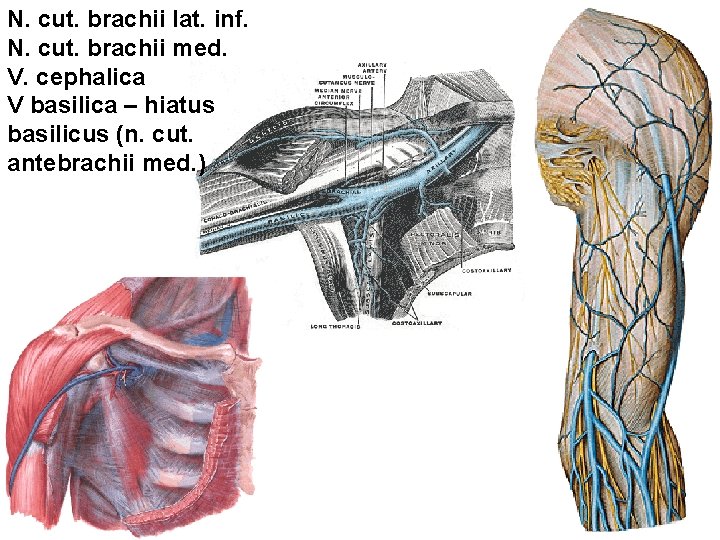

N. cut. brachii lat. inf. N. cut. brachii med. V. cephalica V basilica – hiatus basilicus (n. cut. antebrachii med. )

Septum intermusculare mediale et laterale

Anterior group of muscles: M. biceps brachii caput longum caput breve aponeurosis m. bicipitis brachii M. coracobrachialis M. brachialis N. musculocutaneus

A. BRACHIALIS - a. profunda brachii - a. collateralis ulnaris sup. - a. collateralis ulnaris inf. - a. radialis - a. ulnaris

A. collateralis ulnaris sup. A. collateralis ulnaris inf. N. medianus N. ulnaris